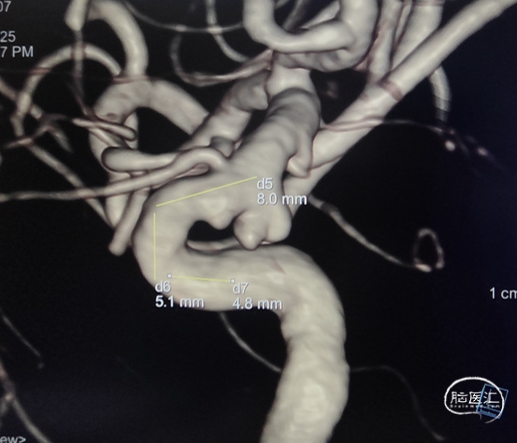

左侧颈内动脉造影:左侧颈内动脉C6段动脉瘤。

左侧颈内动脉三维重建:左侧颈内动脉C6动脉瘤。

术前3D造影